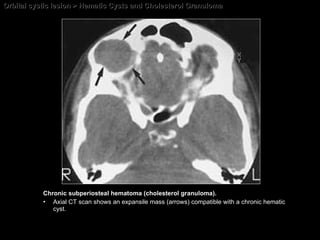

Orbital cystic lesion > Hematic Cysts and Cholesterol Granuloma Chronic subperiosteal hematoma (cholesterol granuloma). Axial CT scan shows an expansile mass (arrows) compatible with a chronic hematic cyst.

Hematic Cysts and Cholesterol Granuloma CT findings of Subperiosteal hematomas Acute hematoma  = sharply defined extraconal, homogeneous, high-density, nonenhancing mass with a  broad base abutting the bone and displacing the peripheral orbital fat .  Chronic hematoma  = sharply defined extraconal,  heterogeneous ,  relatively hypodense , nonenhancing mass.  Long-standing chronic hematic cysts  (cholesterol granulomas) = cystic lesions, associated with  compression bone atrophy  as well as expansion and erosions of adjacent bone.